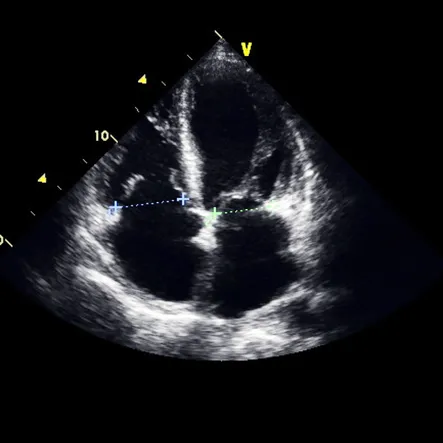

A transthoracic echocardiogram, sometimes abbreviated as an echo, is an ultrasound of the heart. It uses sound waves to generate images of the heart, as well show the flow of blood through different...